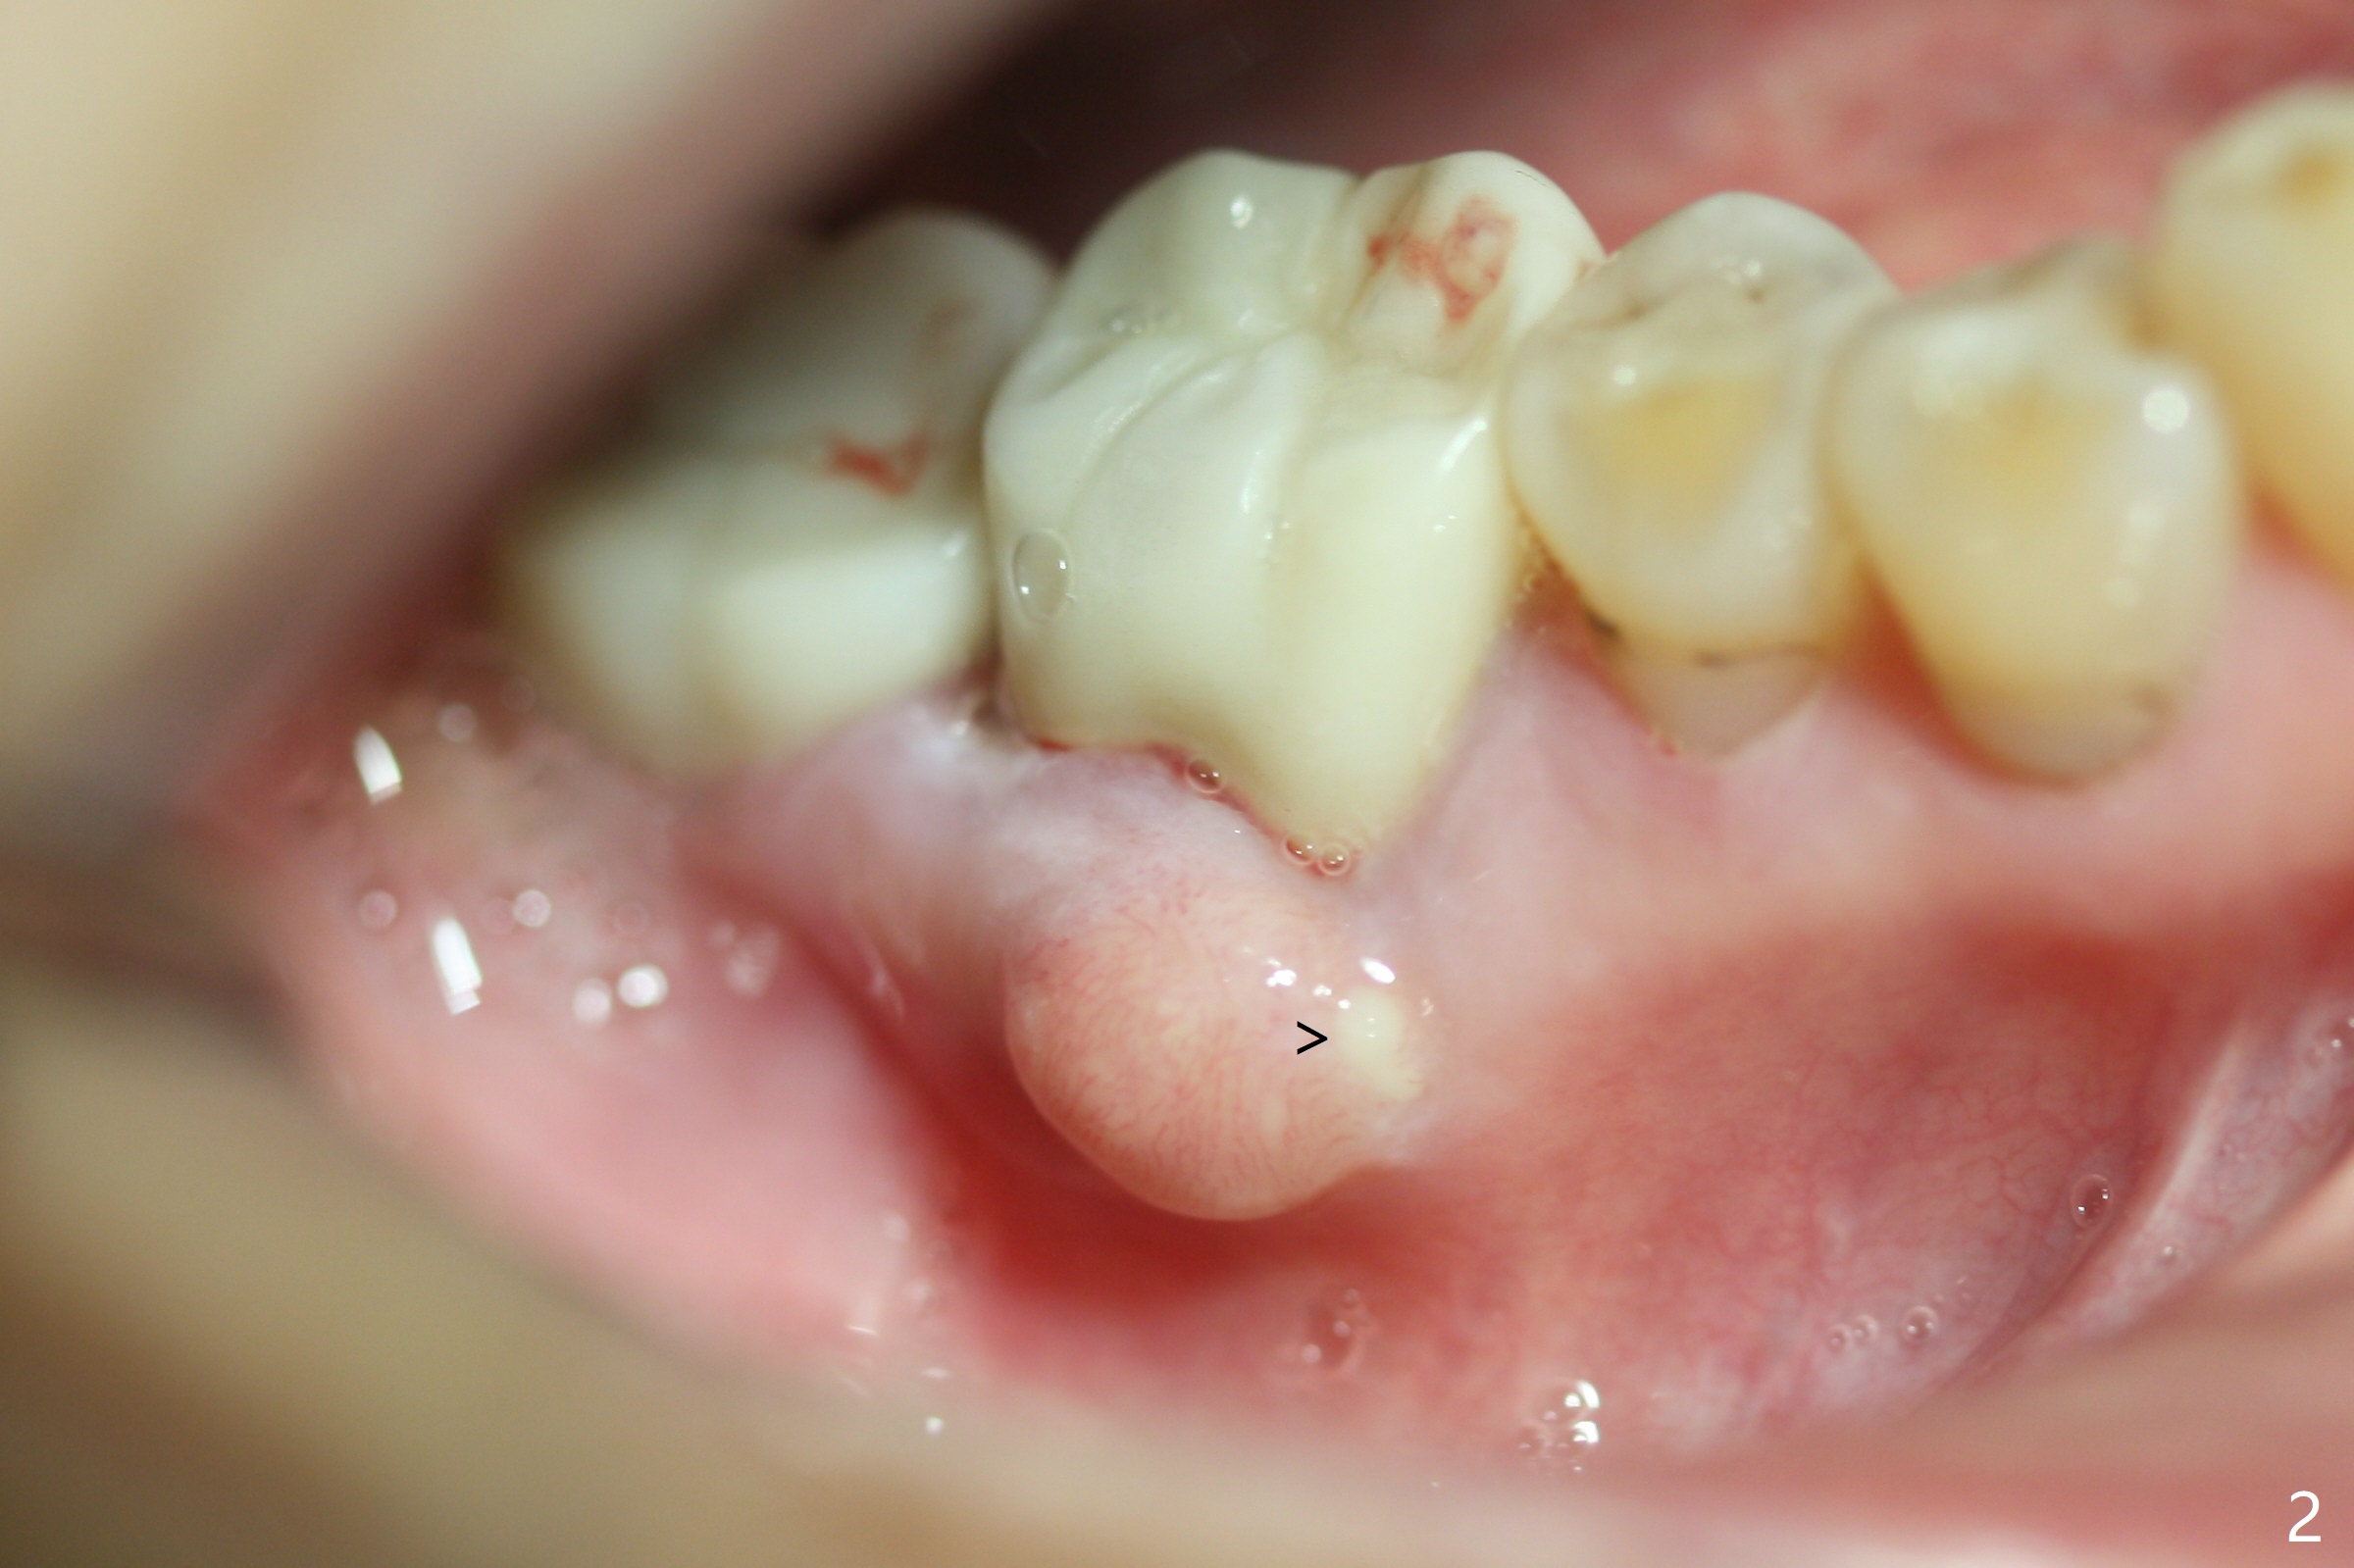

A 67-year-old woman masticates on the right side (Fig.1 (5 years post #30 RCT), as compared to Fig.4,6). One year and 6 months later, there is a fistula mesiobuccal to the tooth #30 (Fig.2 >,4) with mesial root fracture (Fig.3 >). Impression is taken for guide; a 5x11.5 mm implant will be placed slightly distal and lingual to the center of the septum (Fig.5).